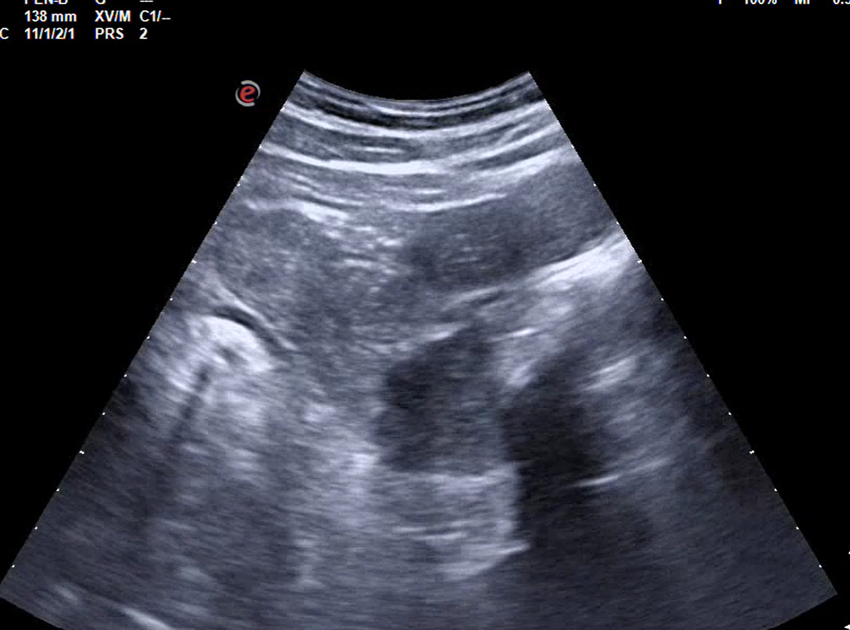

Hombre de 54 años con diarrea y pérdida ponderal: carcinoma de la unión rectosigmoidea.